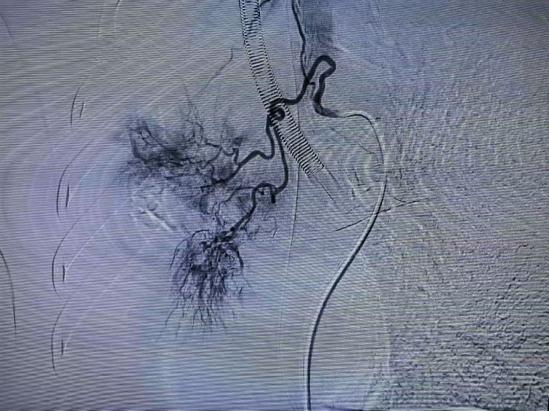

介入科主任雷彦明团队迅速就位,目标是从源头 “堵住” 出血点。在患者氧合尚未完全稳定的情况下,团队通过血管造影迅速定位出血责任血管,随后精准实施支气管动脉栓塞术,用栓塞剂将出血血管 “堵死”,从根源上止住了咯血。